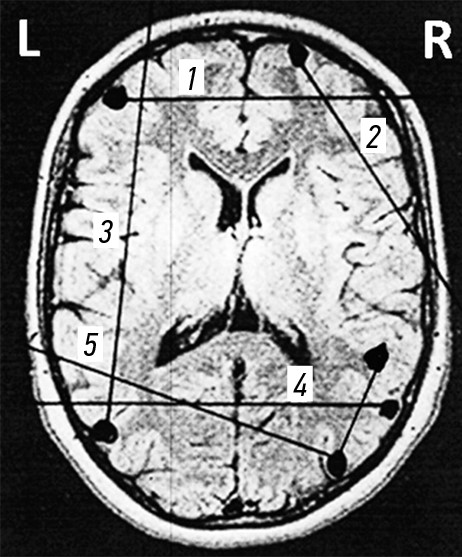

Ходы раневых каналов при огнестрельных проникающих осколочных ранениях черепа и ГМ, также примеры диагнозов продемонстрированы на рис. 3–7.

Рис. 4. Огнестрельные проникающие сегментарные ранения черепа и головного мозга. Примеры диагнозов: 1 — минно-взрывное ранение (МВР). Огнестрельное осколочное слепое (сквозное) проникающее двуполушарное сегментарное ранение лобных долей головного мозга; 2 — МВР. Огнестрельное осколочное слепое (сквозное) проникающее сегментарное ранение правой лобной доли головного мозга; 3 — МВР. Огнестрельное осколочное слепое (сквозное) проникающее сегментарное ранение левой лобной и теменной доли головного мозга; 4 — МВР. Огнестрельное осколочное слепое (сквозное) проникающее двуполушарное сегментарное ранение теменных долей головного мозга; 5 — МВР. Огнестрельное осколочное слепое (сквозное) проникающее сегментарное двуполушарное рикошетирующее ранение левой теменной и правой затылочной доли головного мозга.